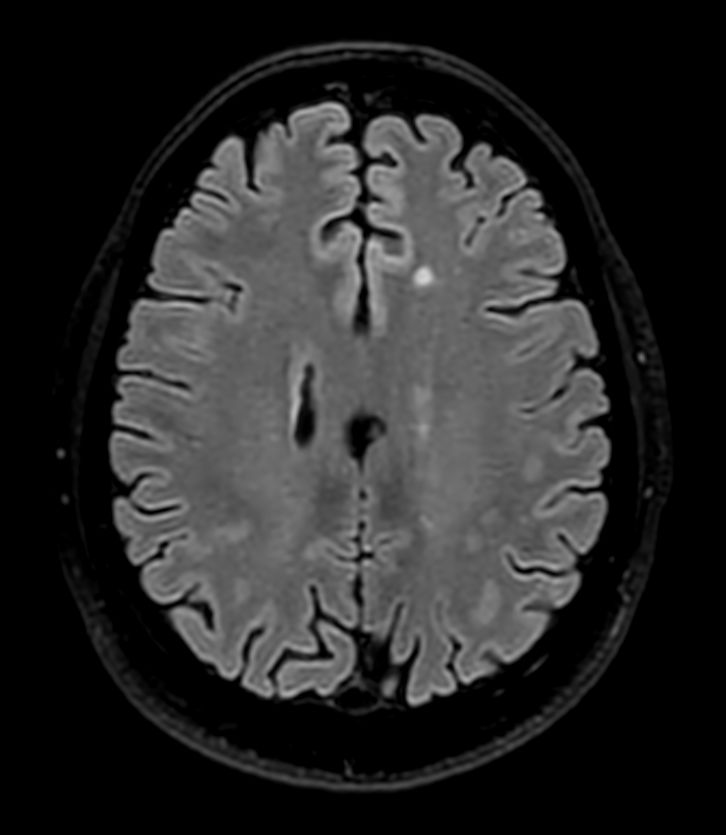

T2w SPAIR Compressed SENSE

3D T1w Black Blood (+gado) Compressed SENSE

3D T1w Black Blood (+gado) (Reformat) Compressed SENSE